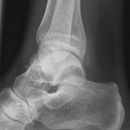

Totale Talusluxation